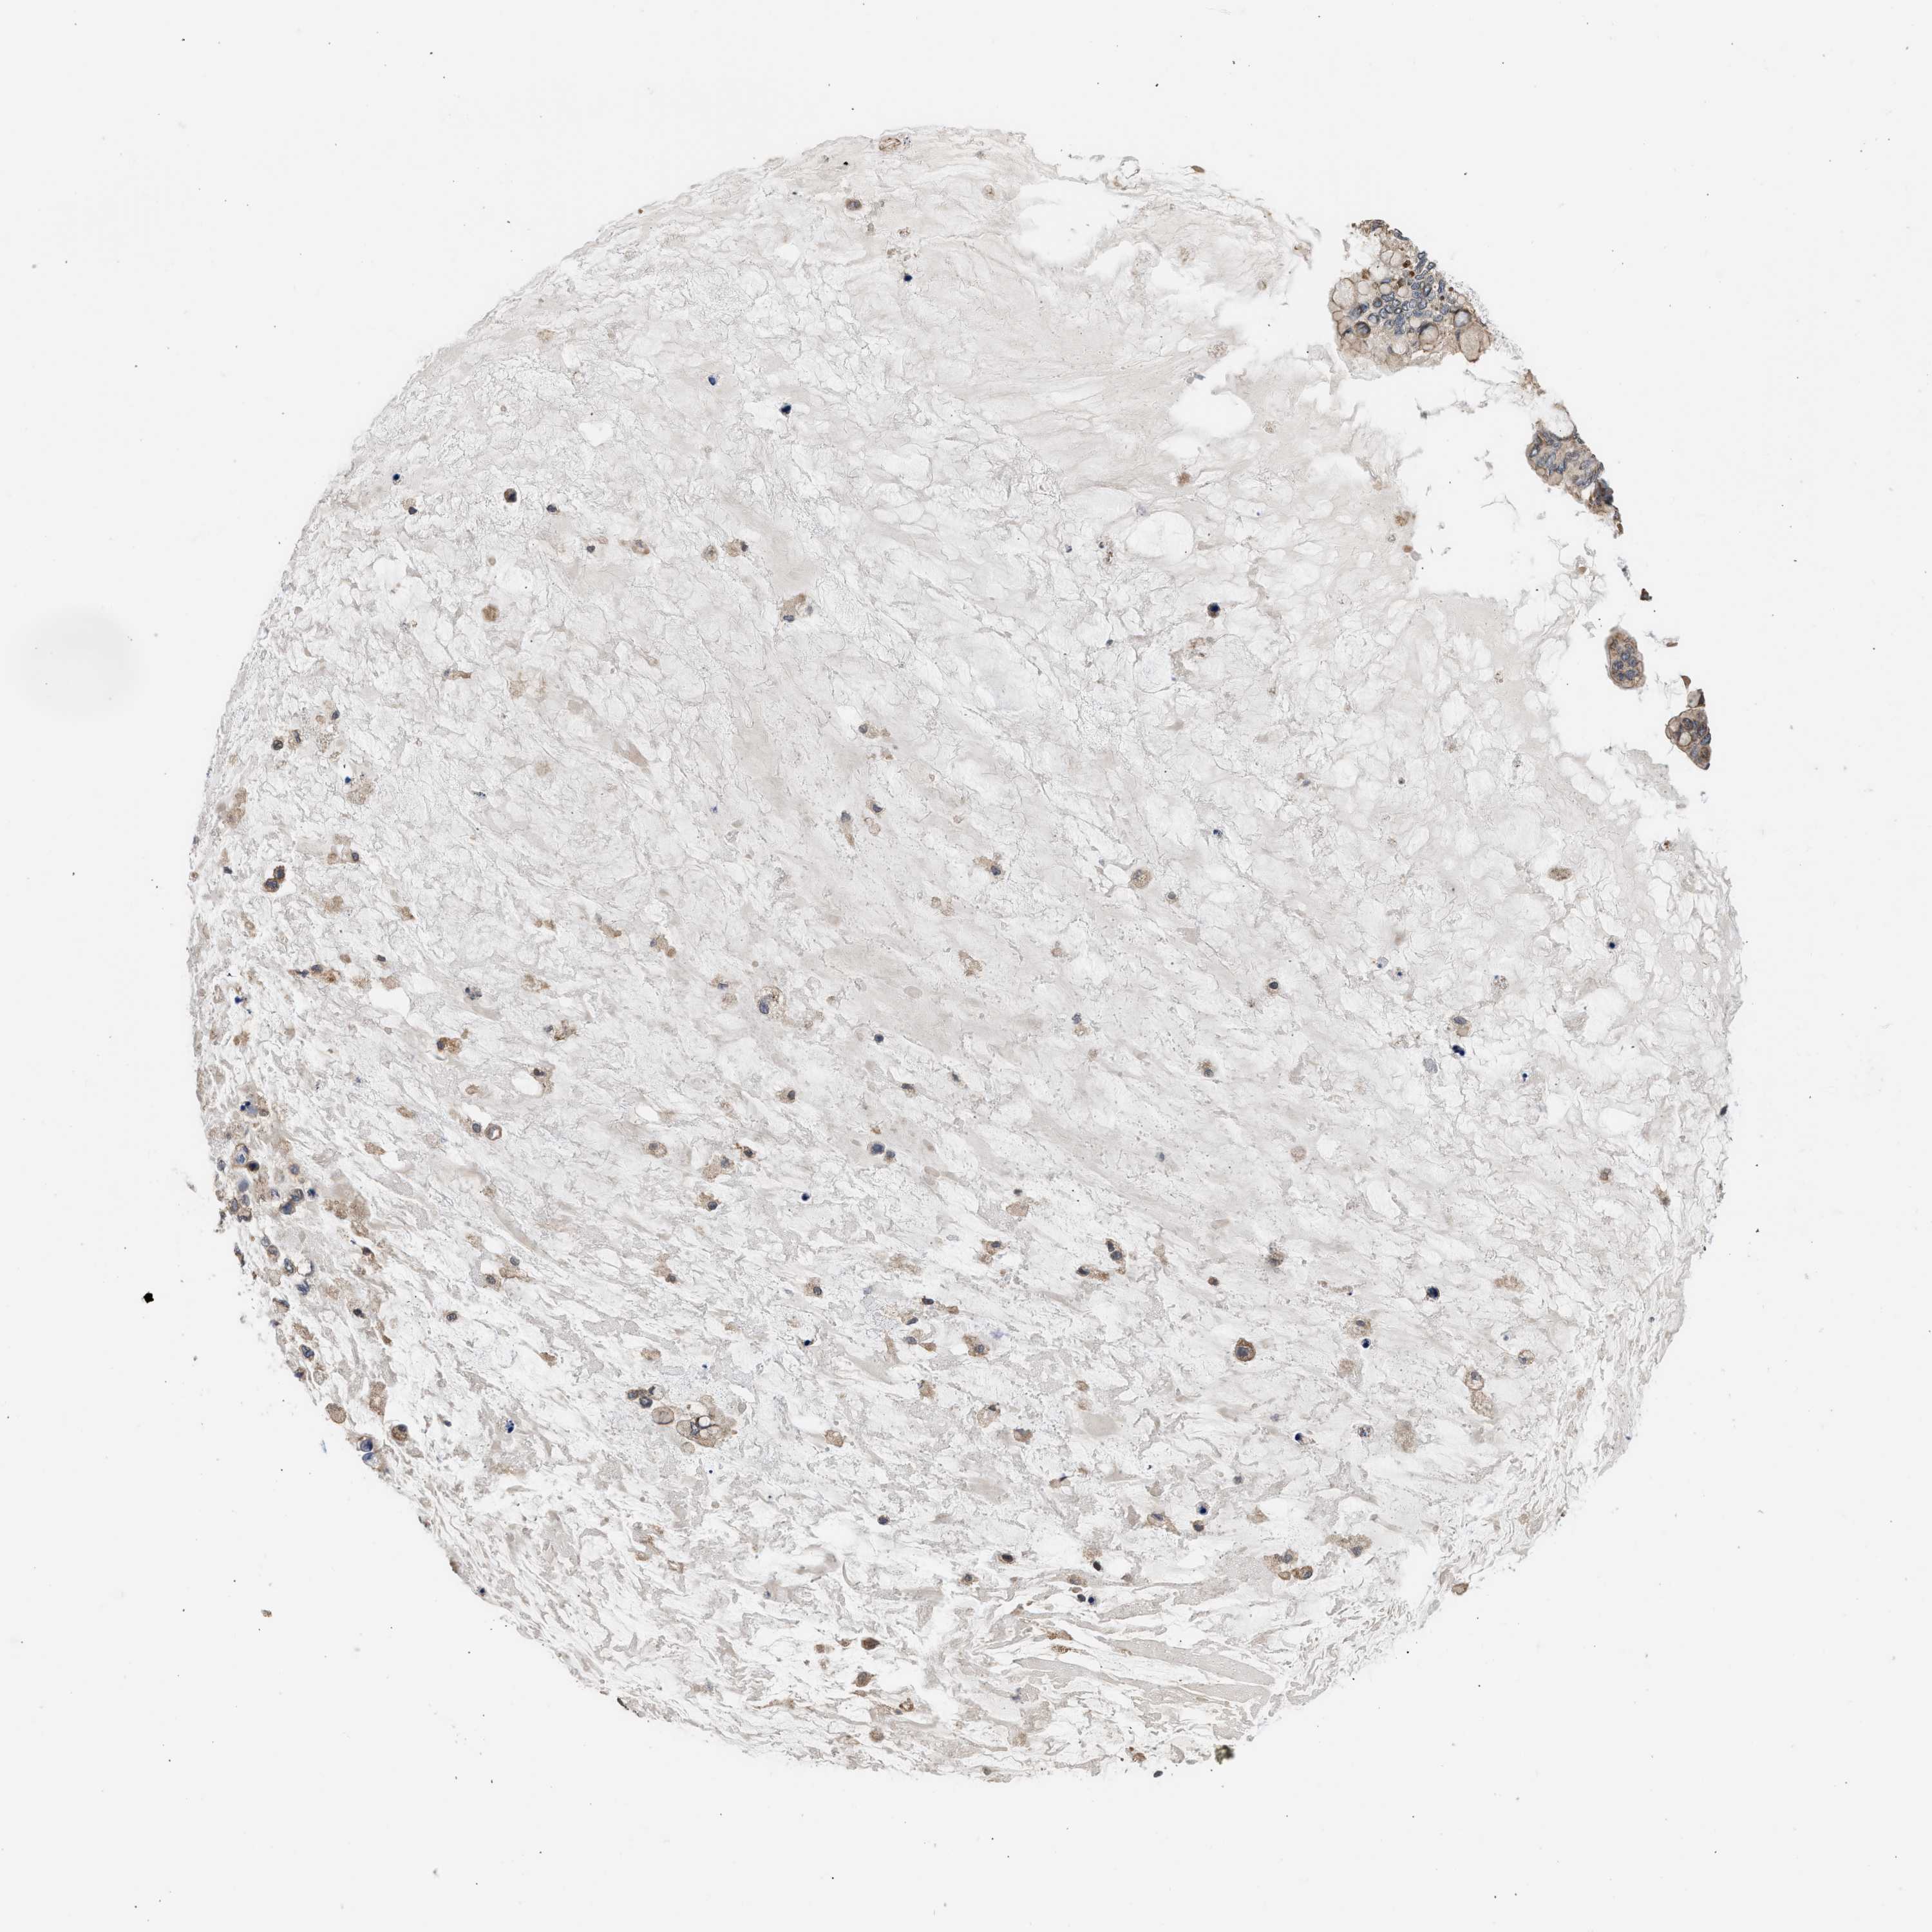

OVARIAN CANCER - Protein expressioni

A mouse-over function shows sample information and annotation data. Click on an image to view it in a full screen mode. Samples can be filtered based on level of antibody staining by selecting one or several of the following categories: high, medium, low and not detected. The assay and annotation is described here.

Note that samples used for immunohistochemistry by the Human Protein Atlas do not correspond to samples in the TCGA dataset.

Antibody stainingi

Antibody staining in the annotated cell types in the current human tissue is reported as not detected, low, medium, or high, based on conventional immunohistochemistry profiling in selected tissues. This score is based on the combination of the staining intensity and fraction of stained cells.

Each image is clickable and will lead to virtual microscopy that enables deeper exploration of all samples and also displays staining intensity scores, fraction scores and subcellular localization as well as patient and tissue information for each sample.

Antibody HPA023202